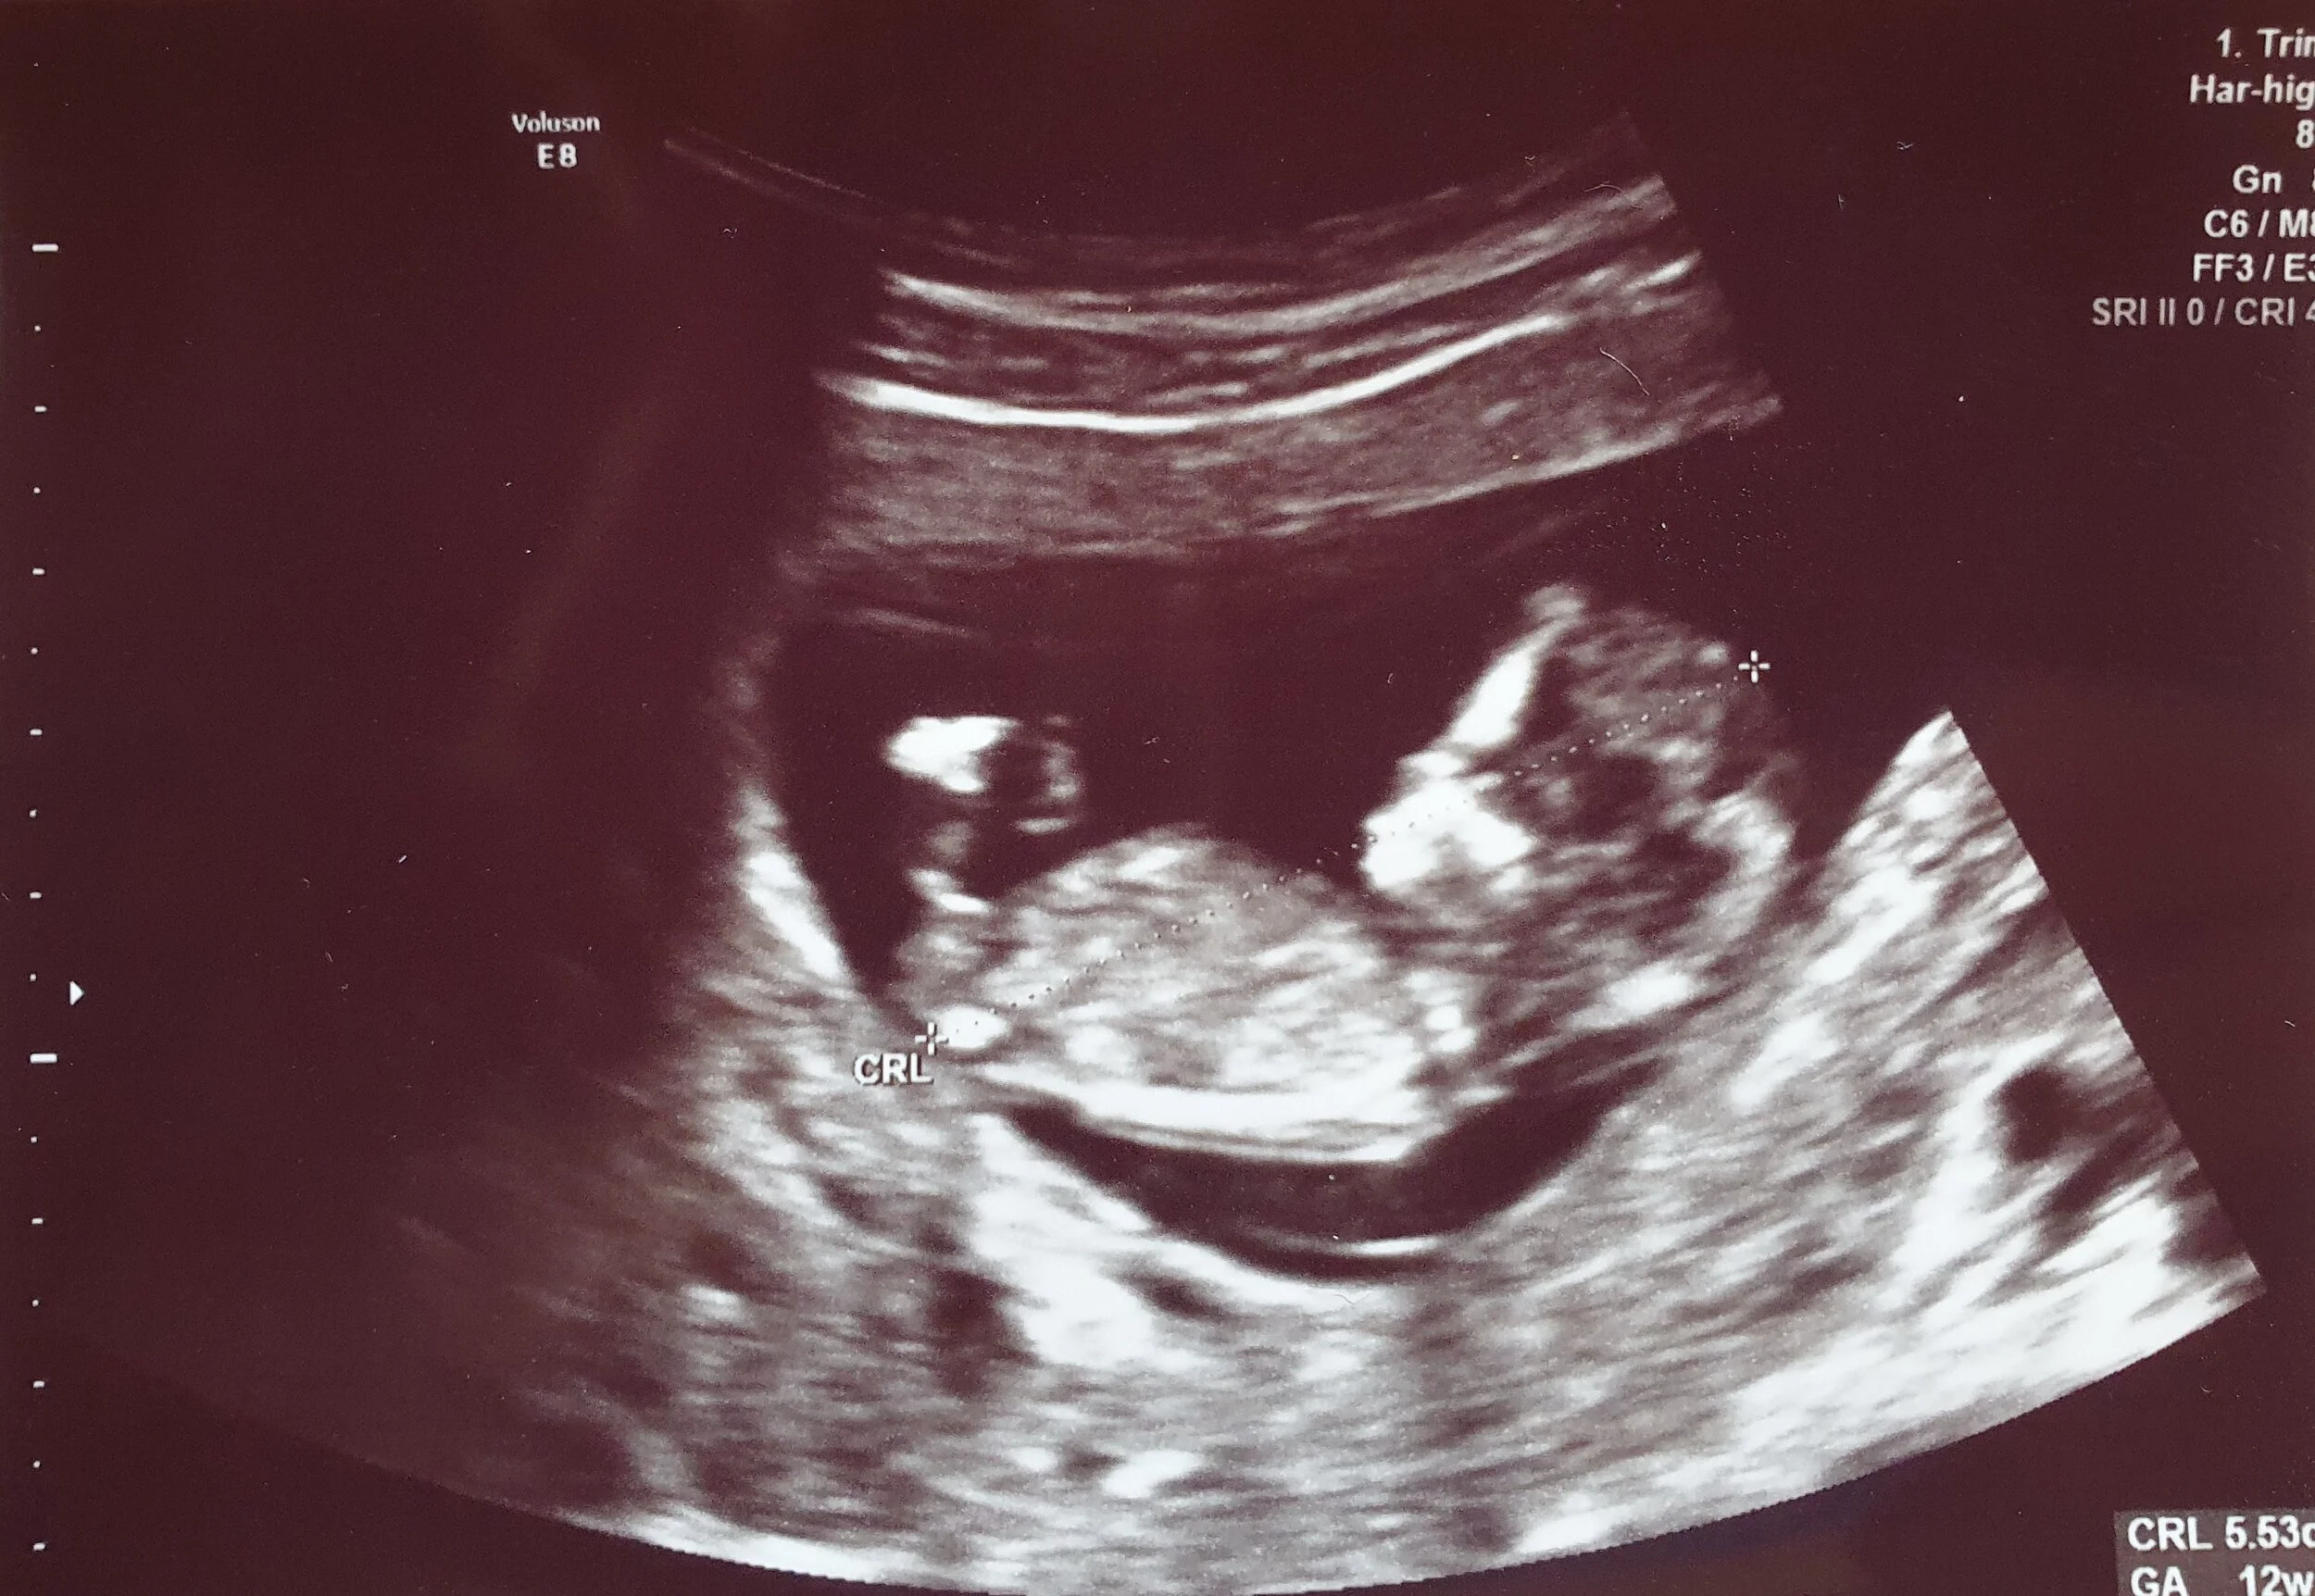

Mary Beth and I found out a short while ago that we are expecting our second child in late September! We are thrilled to be able to announce God’s latest gift to our growing family, with the good news that Mary Beth and the baby are doing wonderfully here at the beginning of her second trimester. We couldn’t be happier.

However, cautious family members and other supporters began to voice another concern to us: if the health system in Belize were to become overrun and overwhelmed by respiratory patients at every hospital and clinic, would Mary Beth and our unborn child be able to get the help they would need in the event that this pregnancy were to develop complications? You may remember that serious issues popped up with Mary Beth’s first pregnancy with Austin, and if similar (or other) problems were to come about, would an overtaxed and flooded emergency health system be able to give her the care and attention that she and this growing baby would need?